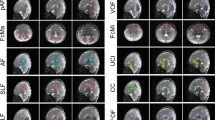

Figure 4 shows the 3D projection of different fiber bundles on midsagittal plane at different ages.

Demonstration of methodology used for tract reconstruction from 7-y old healthy subject. (A) Sagittal CC and coronal SLF, ILF, CNG, and Fx stable fiber mass maps (first row) showing selection of planes for the reconstruction of respective right tract. (B) Demonstration of methodology used for motor (first row) and sensory tract (second row) reconstruction.